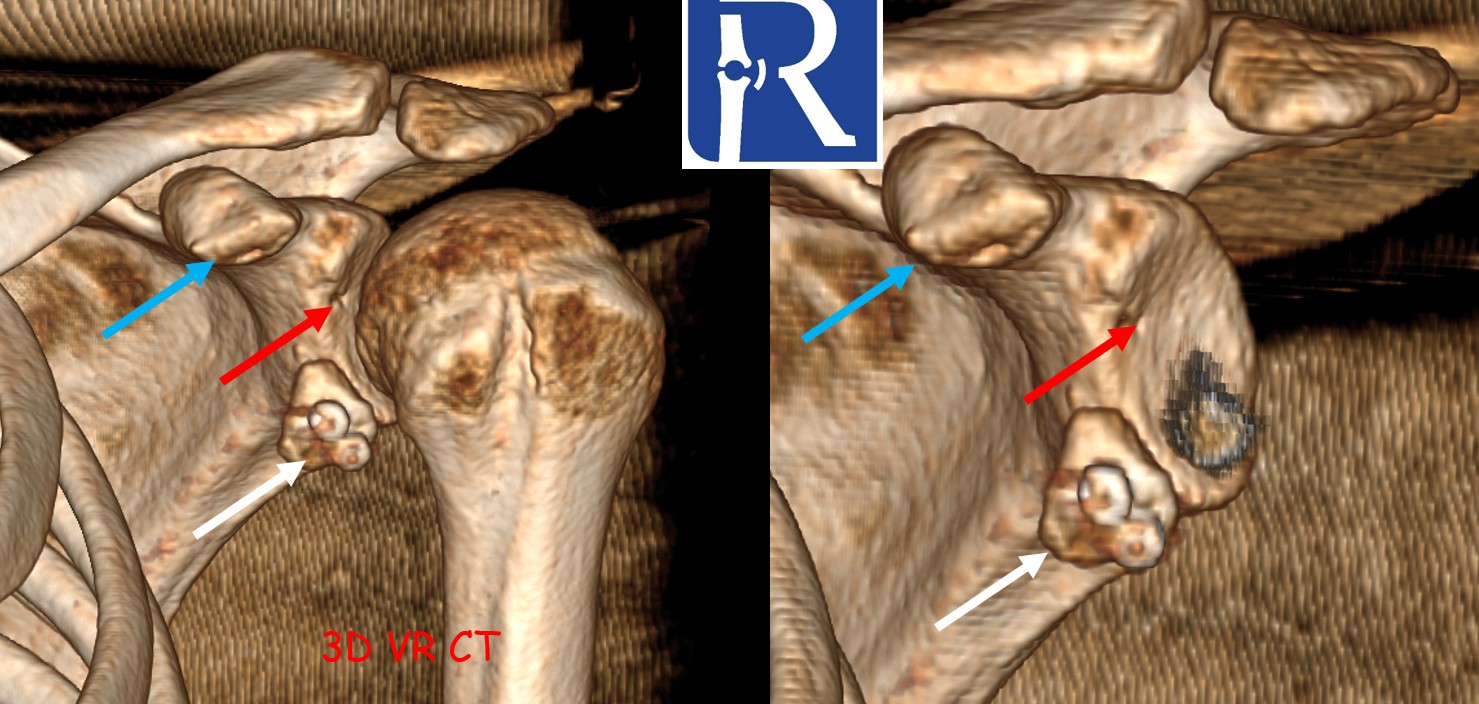

Case Summary A 70-year-old male presented with shoulder pain after a fall. Initial computed tomography (CT) demonstrated a linear, nondisplaced fra ...